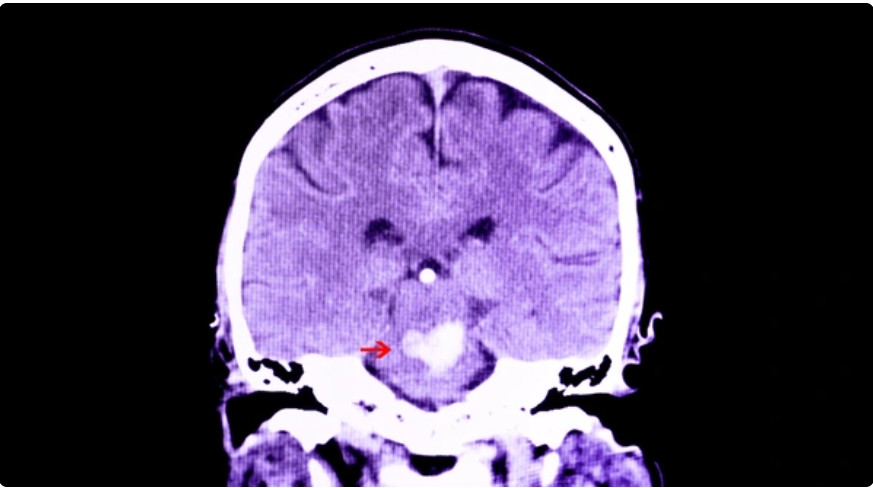

1.뇌간의 뇌교에서 발생하는 출혈로, 전체 뇌내출혈의 약 10%를 차지하지만 가장 치명적인 예후를 보이는 질환 중 하나임.

5.뇌교는 공간이 매우 제한적이며, 주위가 중요 신경핵과 상행, 하행 신경로로 밀집됨.

출혈 발생시 주변 신경조직을 압박 + 파괴하여, 소량 출혈이라도 임상적으로 치명적임.

8.출혈 자체와 주변 뇌부종 증가로 뇌간이 압박되면 뇌실로 출혈 파급되거나 급성 폐쇄성 수두증 발생할 수 있음.

9.피질척수로 손상으로 사지마비, 안구운동 핵 및 경로 침범으로 동공 이상, 안구운동 장애가 나타남.